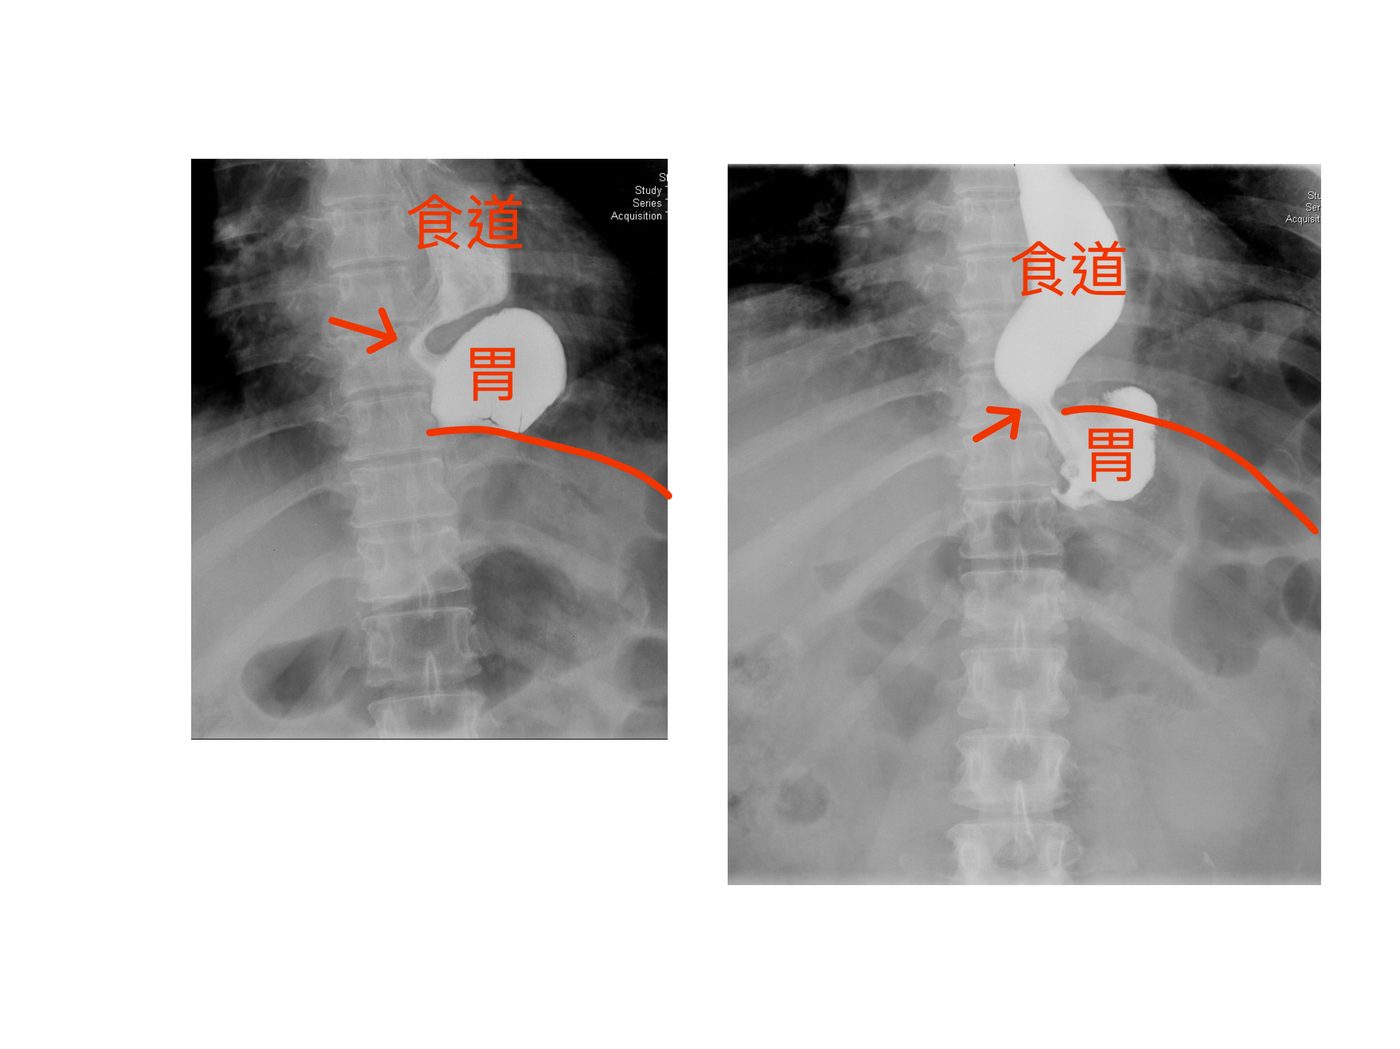

入院後進行完整評估,包含胃鏡、電腦斷層及上消化道攝影(UGI series),發現以下關鍵問題:

Comprehensive workup including upper endoscopy, CT scan, and upper GI series (UGI) revealed three critical findings:

⚠️ 食道裂孔疝氣復發:Recurrent Hiatal Hernia:

原本修補的疝氣再度復發,部分胃組織再次滑入縱隔腔,造成食道與胃交接處嚴重扭曲,食物無法順利進入胃管。

The previously repaired hernia had recurred. Gastric tissue had re-herniated into the mediastinum, severely distorting the oesophagogastric junction and preventing food from passing freely into the sleeve.

▲ 上消化道攝影(UGI):可見食道(食道)與胃(胃)的相對位置,箭頭所指為胃體滑入縱隔腔的位置,造成食道胃交接處受壓阻塞。

▲ Upper GI series (UGI): the images show the oesophagus (食道) and stomach (胃). Arrows indicate the portion of stomach herniated into the mediastinum, compressing and obstructing the oesophagogastric junction.